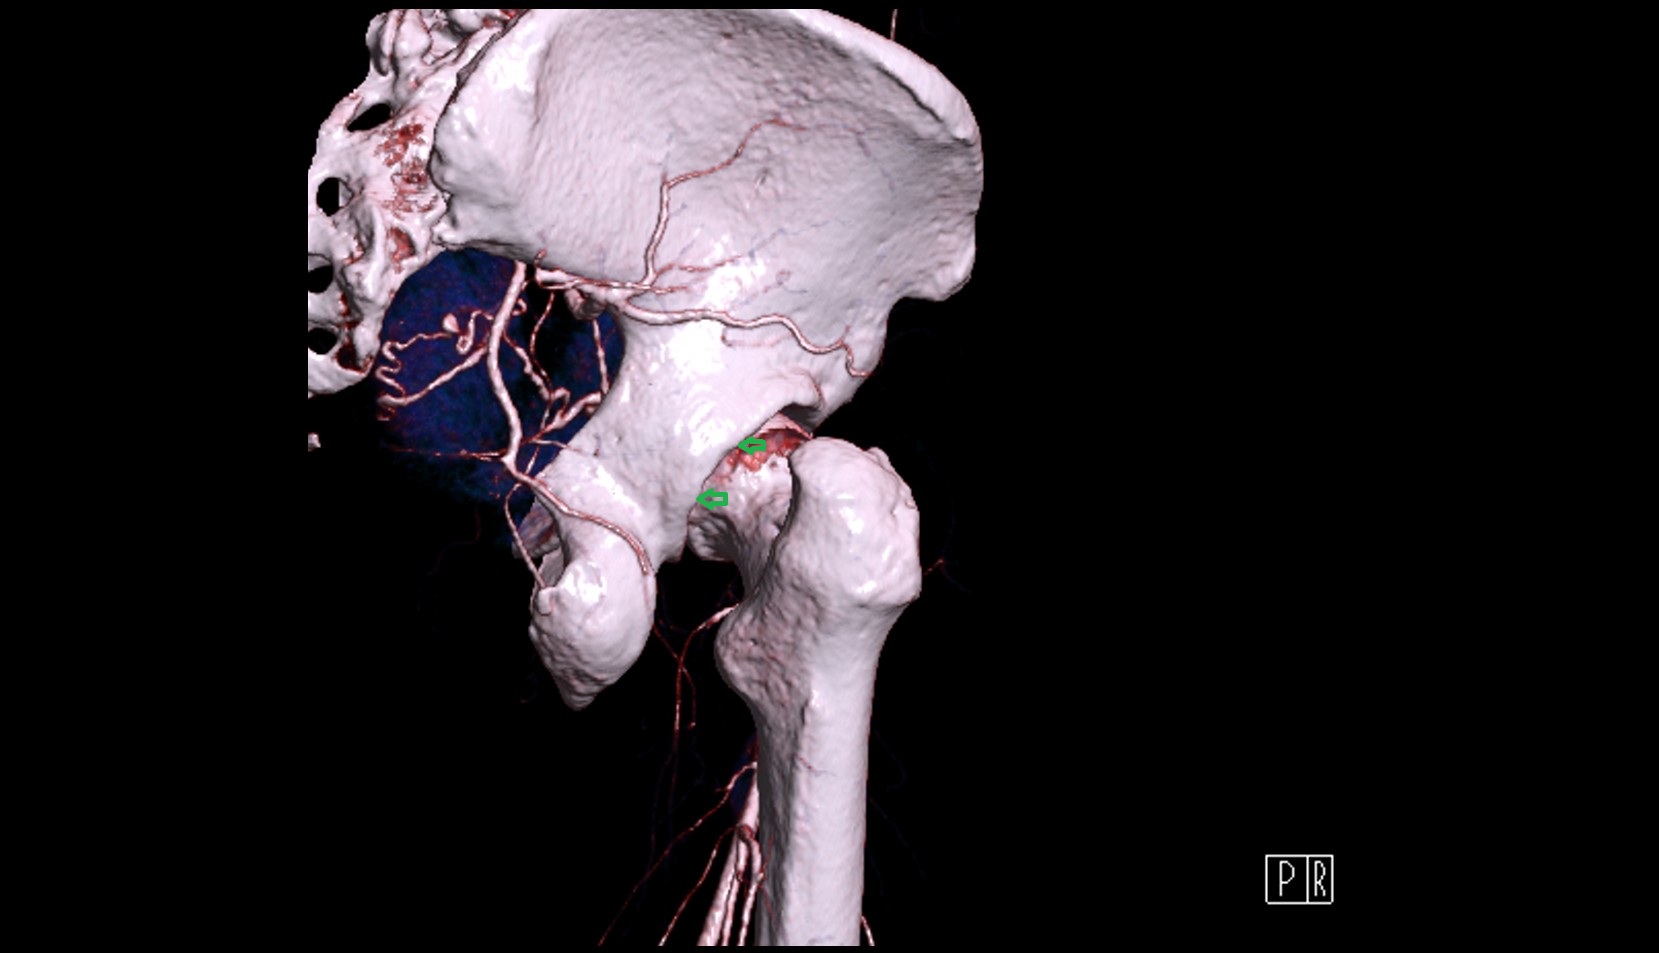

- Acetabular margin (Acetabular rim)

- Acetabulum

- Head of femur

- Hip joint